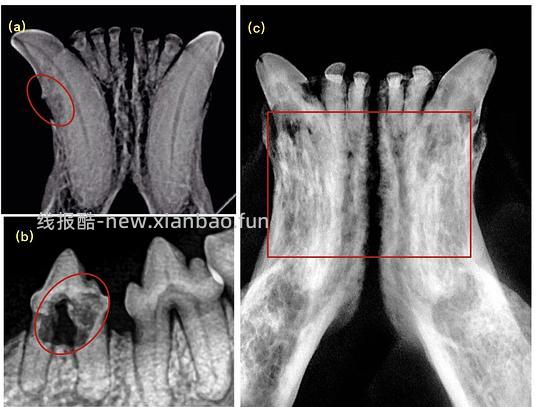

4.2 猫牙吸收的类型 — 依据X光片特点

口腔内X光牙科片在诊断和确定治疗计划上起着重要作用。根据在影像学上表现出的特点,牙吸收可分为三种类型如下(图10)[1, 18]:

![【科普】[养猫笔记05-医疗] 猫牙破齿细胞吸收性损伤(FORL)— 猫第二大常见疾病 - 线报酷 【科普】[养猫笔记05-医疗] 猫牙破齿细胞吸收性损伤(FORL)— 猫第二大常见疾病 - 线报酷](https://new.xianbao.fun/plus/api/image.php?imgurl=https://img2.doubanio.com/view/group_topic/m/public/p645120490.jpg)

图*10(a)1型牙吸收(b)2型牙吸收(c)3型牙吸收[18]

Type1(T1): 对于具有1型吸收牙齿的X射线照片,该牙齿呈现局灶性or多灶性射线可透过性,其他部分则保持正常的射线不透性及正常的牙周韧带结构 - 图10(a)+图11

Type2(T2): 对于具有2型吸收的牙齿,牙周韧带间隙至少在某些区域变窄或者消失,部分牙齿的射线不透性降低 - 图10(b)+图12

Type3(T3): 3型吸收的牙齿在同一颗牙上具有1型和2型的特点,即受影响的牙齿既存在牙周韧带间隙的狭窄/丢失,也同时存在局灶性or多灶性射线可透过性和牙齿其他区域射线不透性降低 - 图10(c)+图13